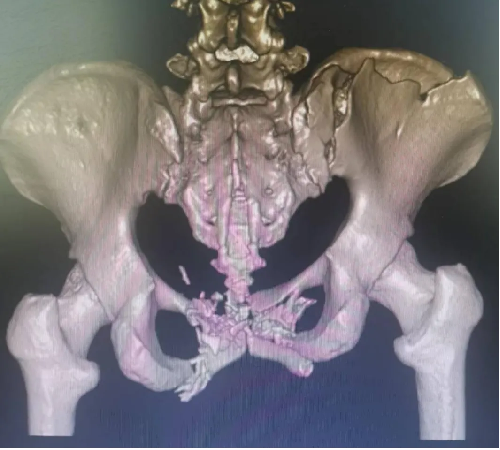

患者黄某,因车祸外伤导致全身多处疼痛入院,入院即因失血性休克于ICU监护,完善检查显示双侧耻骨粉碎性骨折、右侧髂骨多处骨折、右骶髂关节脱位,提示骨盆前-后环均不稳定。

对于此种前后环均严重失稳的复杂骨盆骨折的治疗,保守治疗不仅需长期卧床,易导致褥疮、肺部感染、泌尿系感染及深静脉血栓风险,同时势必影响后期功能恢复,严重降低患者未来生活质量。传统开放术式手术切口大、手术时间长,手术难度极大,同时存在盆腔内血管神经及膀胱的医源性损伤风险,以往,遇到此种严重病情只能依赖上级医院专家来院手术指导,但基于近期成功开展的骨盆微创治疗的经验支持,外一科董明主任反复研究患者病情及影像,充分考虑手术创伤与风险后,决定开展骨盆骨折有限切开复位内固定术。

经充分术前准备,由董明主任、余策略主治医师、叶强医师为患者在全麻下仅用不到2小时便成功完成了手术,术中出血量少,术后第二天患者就可以床上坐起及翻身,功能恢复良好。